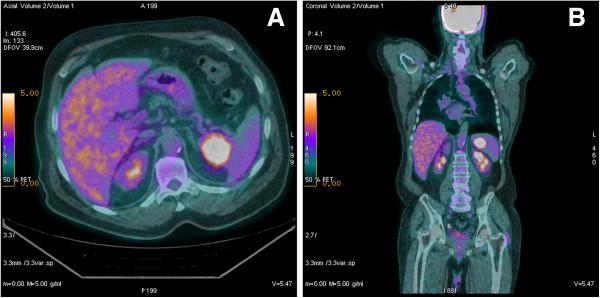

Carcinoma ex pleomorphic adenoma is a rare tumor arising from the salivary glands that spreads through direct extension, through the lymphatic vessels, and, rarely, hematogenously. When distant metastases have been found, they have been reported mainly in the lung. We present an unusual case of carcinoma ex pleomorphic adenoma of the parotid gland with splenic metastases. The patient presented with a primary carcinoma ex pleomorphic adenoma of the parotid gland and he underwent a total parotidectomy with laterocervical lymphadenectomy ipsilateral and adjuvant radiation therapy to the right parotid area. One year later, the patient showed an ipsilateral supraclavicular lymph node recurrence, treated with surgery and radiation therapy. Two more years later, the patient developed lung and splenic lesions, detected through CT and PET. He underwent splenectomy and pathologic assessment of the specimen showed metastatic carcinoma ex pleomorphic adenoma. To our knowledge, there is no reported case of a carcinoma ex pleomorphic adenoma metastasizing to the spleen. Patients treated for carcinoma ex pleomorphic adenoma should be investigated for distant metastases with a long-term follow-up examination for local and distant metastases and new splenic lesions in these patients should be investigated.

多形性腺瘤恶变是一种罕见的起源于唾液腺的肿瘤,其扩散途径包括直接蔓延、通过淋巴管,很少通过血行转移。当发现远处转移时,主要报道为肺转移。我们报告一例腮腺多形性腺瘤恶变伴脾脏转移的罕见病例。该患者最初表现为腮腺原发性多形性腺瘤恶变,接受了腮腺全切术、同侧颈侧区淋巴结清扫术以及右侧腮腺区辅助放疗。一年后,患者出现同侧锁骨上淋巴结复发,接受了手术及放疗。又过了两年,患者通过CT和PET检查发现肺部及脾脏病变。他接受了脾切除术,标本的病理评估显示为多形性腺瘤恶变转移癌。据我们所知,尚无多形性腺瘤恶变转移至脾脏的报道。接受多形性腺瘤恶变治疗的患者应进行长期随访以排查远处转移,对于这些患者出现的新的脾脏病变也应进行排查。